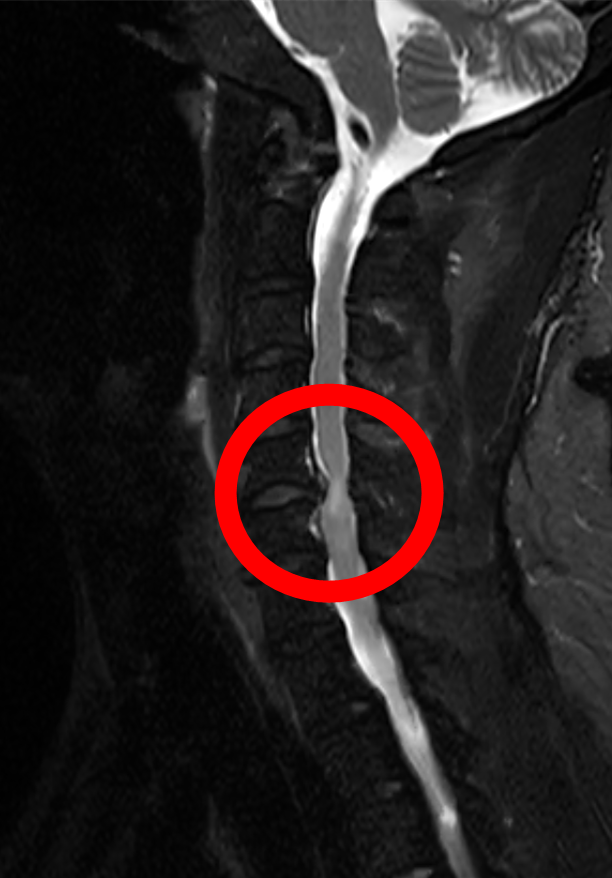

李先生谈及患病经历时满是感慨:“自从得了颈椎病,实在是太痛苦了,颈肩部疼痛,双上肢持续疼痛麻木,让人难以忍受,近期夜间更是因疼痛辗转难眠。”为缓解病痛,他尝试过口服中药、西药、理疗等多种保守治疗,但症状反复发作且逐渐加重,多次求医问诊效果均不理想。经我院脊柱外科团队详细检查,李先生被确诊为“颈椎间盘突出(C5-6 节段)伴脊髓压迫”。医生明确告知,若不及时手术,可能导致神经不可逆损伤,甚至出现瘫痪症状,需尽快干预治疗。

“传统颈椎融合术虽然能解除压迫,但失去一个椎间盘的活动单元后颈椎活动度会有减少,而李先生仅 45 岁,对颈椎活动需求比较高。” 经我院脊柱外科团队反复研讨,结合李先生的年龄和对颈部活动功能的需求,最终决定采用人工颈椎间盘置换术这一先进术式。该技术作为目前国际脊柱外科的主流前沿技术,打破了传统手术 “融合固定”的局限,具有技术更先进、创伤更微小、恢复更快捷三大核心优势。仿生假体模拟天然椎间盘功能,保留颈椎活动度,降低远期并发症风险;小切口、少出血,减少组织损伤和术后疼痛;术后无需长期制动,患者能快速回归正常工作生活。通过植入仿生人工椎间盘,既能彻底解除神经压迫,又能完整保留颈椎的屈伸、旋转功能,从根本上避免了传统手术带来的颈部僵硬问题。